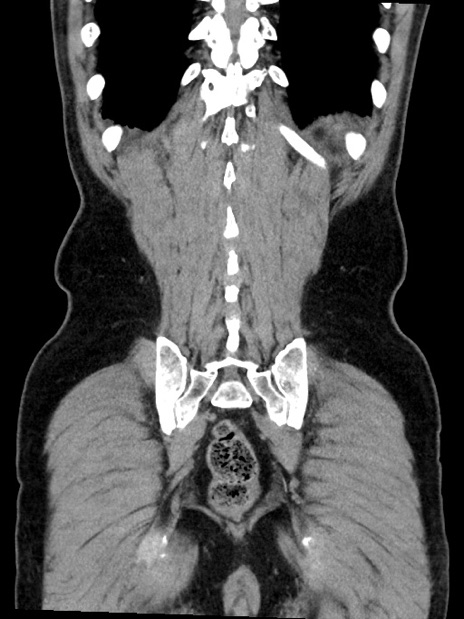

症例35(冠状断像)